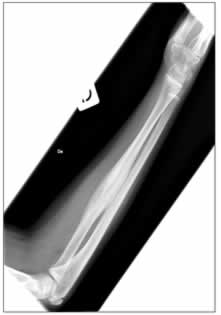

A distanza di un anno (2004) C. ritorna nuovamente alla nostra attenzione per la comparsa di febbricola accompagnata da dolori agli arti inferiori, in particolare a destra, con indici di flogosi aumentati e rilievo obiettivo di sfumato deficit di forza all'arto inferiore destro, su base antalgica .L'ecografia e la radiografia dell'arto inferiore destro mostrano rispettivamente un minimo versamento articolare a livello della coxo-femorale e un aspetto del femore, sempre a destra, di marcato ispessimento della corticale ossea, come da reazione periostale, con una relativa iperdiafania della spongiosa. (figura 2)

Figura 2: radiogramma del femore che mostra, al III medio, marcato aumento di spessore della corticale ossea sul versante interno